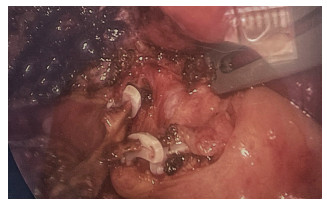

先后将2支胆囊管,分别在距离胆总管0.5 cm处用1枚血管夹夹闭,再于其近端夹1枚血管夹,于2枚血管夹之间切断胆囊管(图 4)。用电凝钩行胆囊浆膜下剥离并切除胆囊,胆囊床电凝止血,于温氏孔放置引流管,完成三孔法腹腔镜胆囊切除术。

图  4   术中使用血管夹分别夹闭上、下2支胆囊管